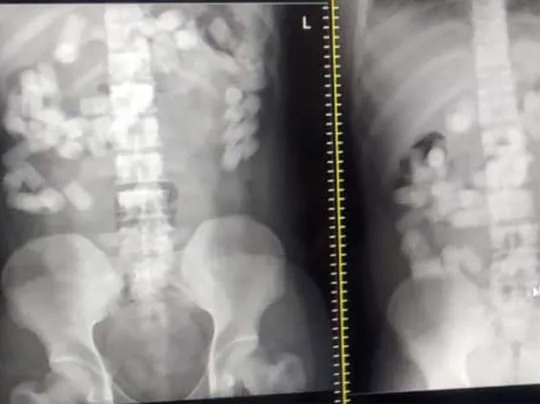

अभी तक की जानकारी के मुताबिक, एयरपोर्ट से गिरफ्तार विदेशी नागरिक ने पेट में कुल 70 कैप्सूल निगल लिया था. जे जे अस्पताल में सभी कैप्सूल निकालने की प्रक्रिया चल रही है. कैप्सूल में कोकीन भरी हुई है. इससे पहले, एनसीबी ने पिछले महीने मुंबई में एक महिला को गिरफ्तार किया था और उसके पास से करीब एक करोड़ रुपये मूल्य के प्रतिबंधित मादक पदार्थ ”हशीश” जब्त किया था. एजेंसी ने बताया था कि जब्त किया गया प्रतिबंधित पदार्थ जम्मू कश्मीर से यहां लाया गया था.